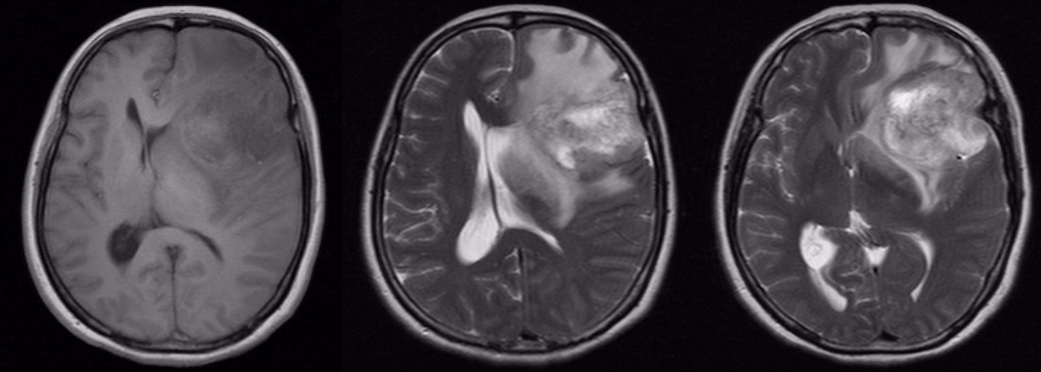

术中荧光染色情况

(黄荧光辅助成像技术切除脑胶质瘤手术视频一)

术中肿瘤荧光染色及止血情况

(黄荧光辅助成像技术切除脑胶质瘤手术视频二)